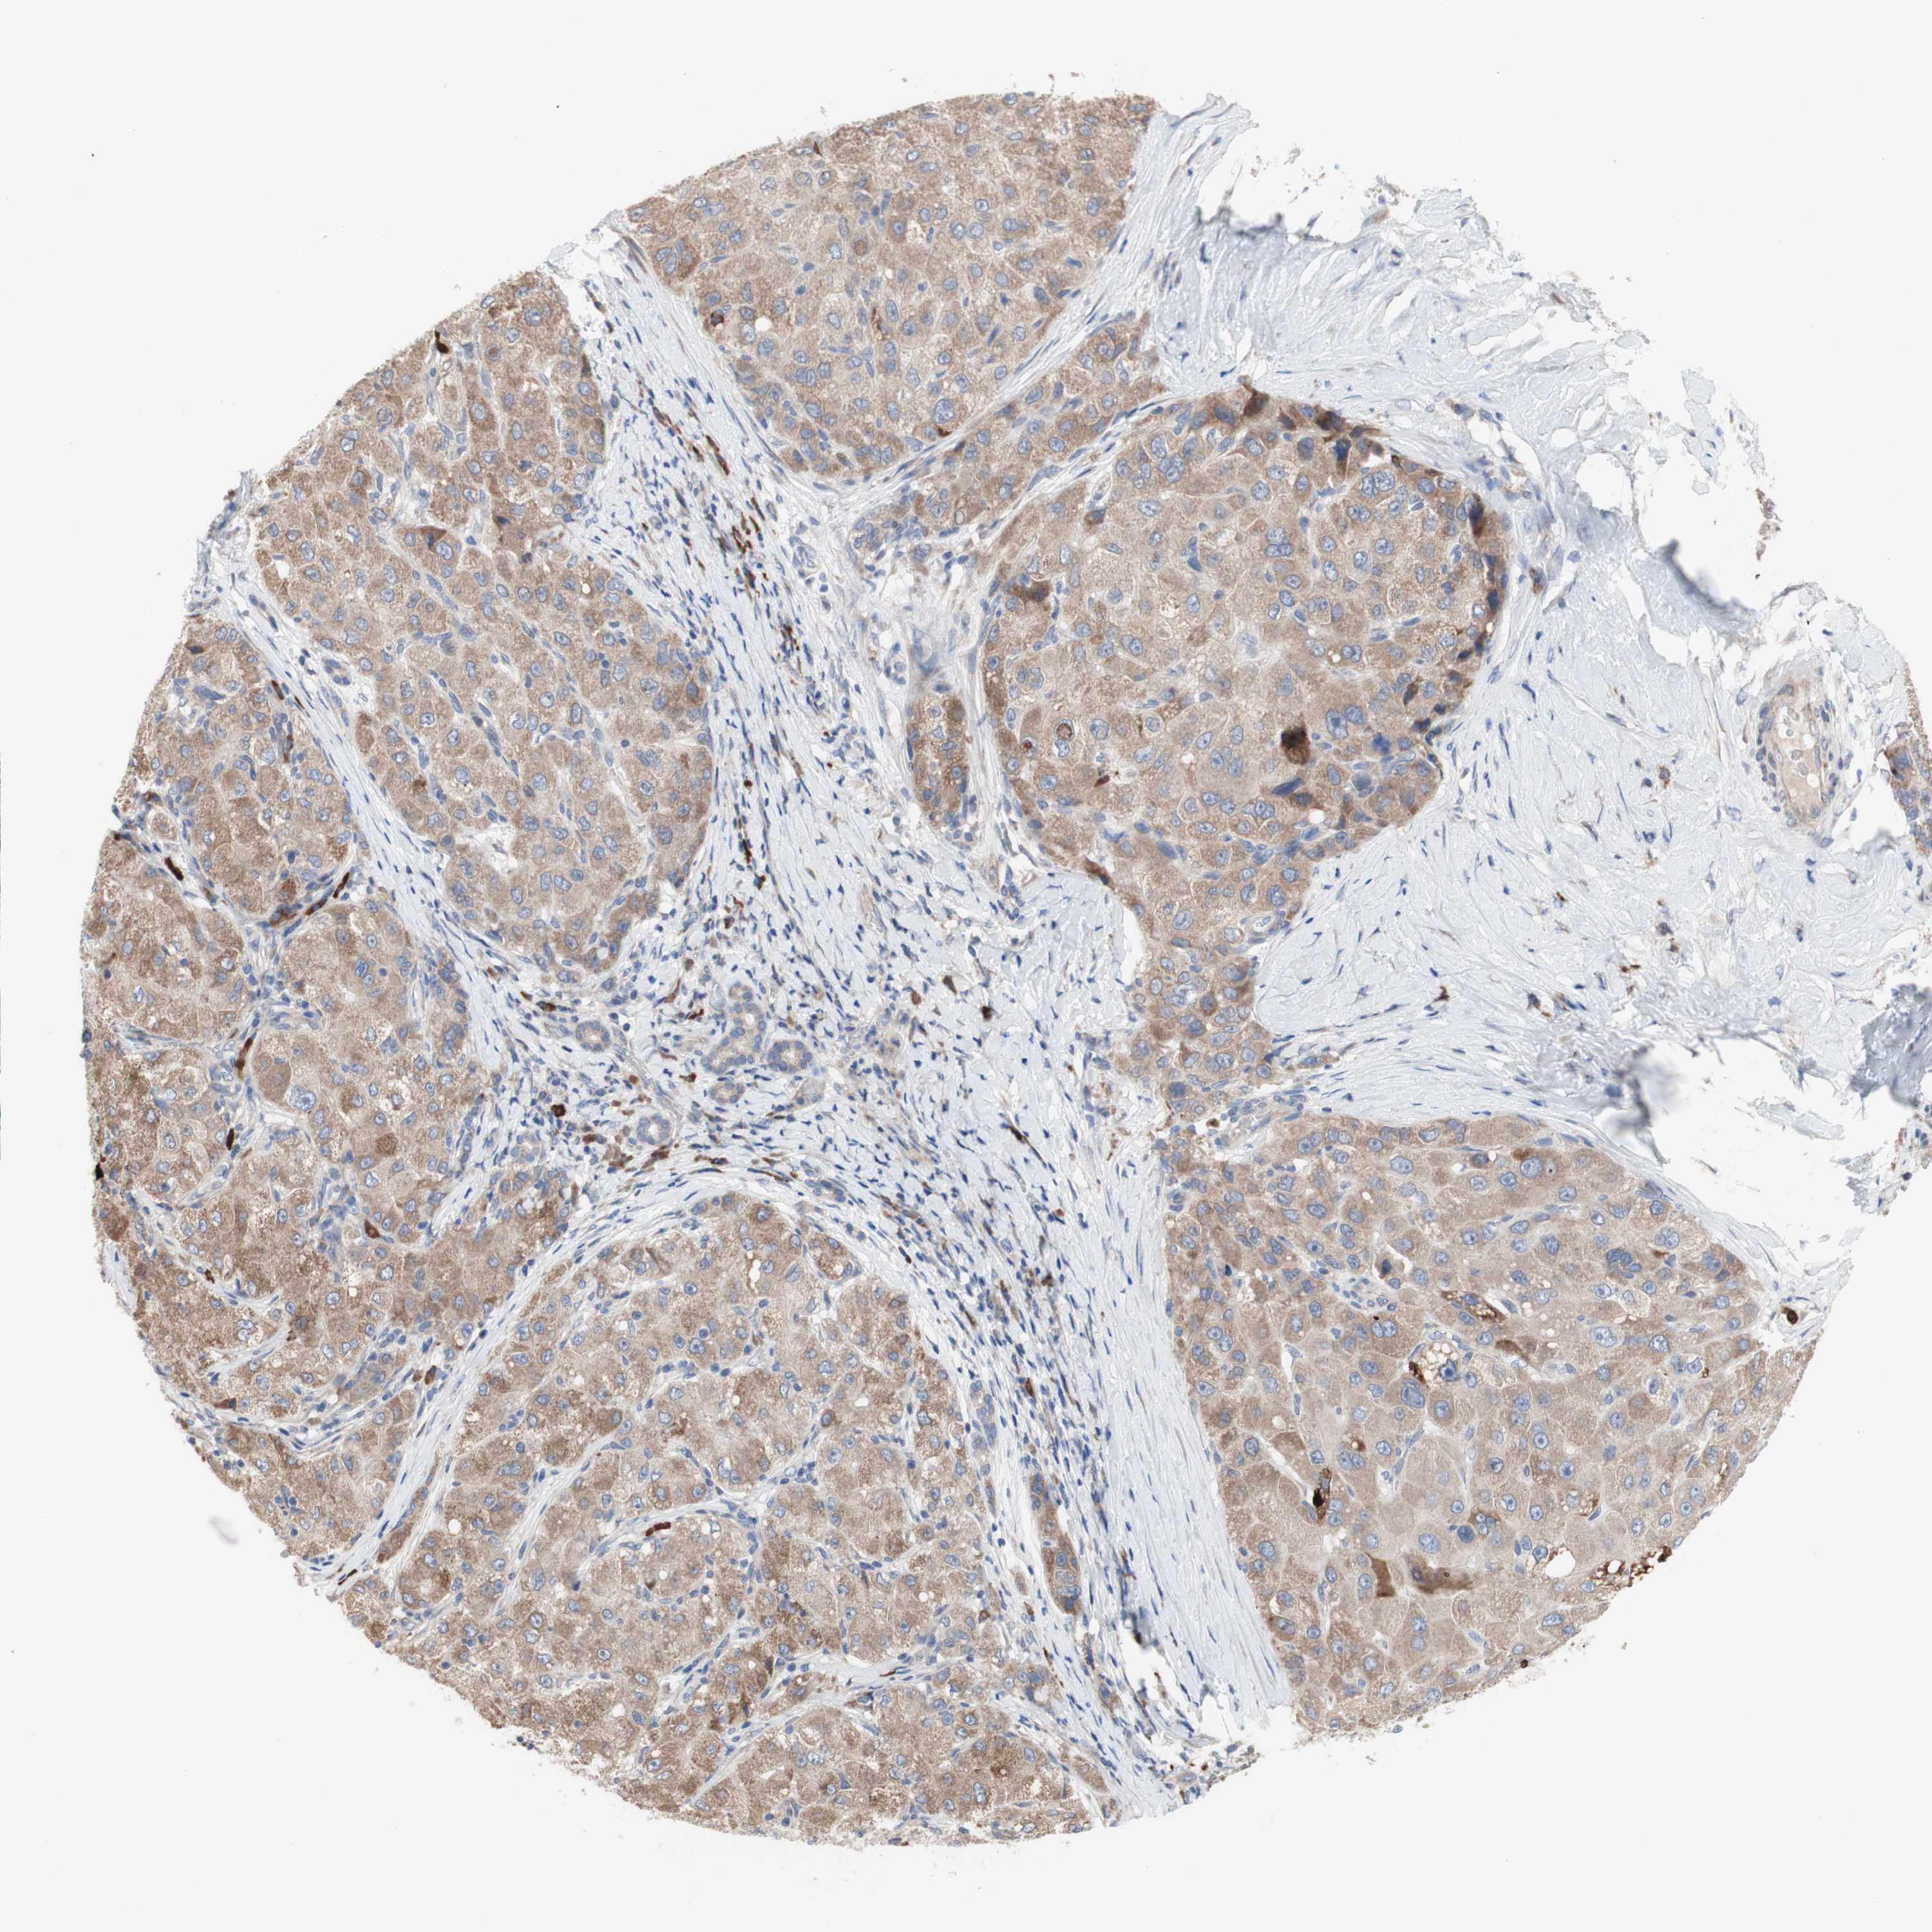

LIVER CANCER - Protein expressioni

A mouse-over function shows sample information and annotation data. Click on an image to view it in a full screen mode. Samples can be filtered based on level of antibody staining by selecting one or several of the following categories: high, medium, low and not detected. The assay and annotation is described here.

Note that samples used for immunohistochemistry by the Human Protein Atlas do not correspond to samples in the TCGA dataset.

Antibody stainingi

Antibody staining in the annotated cell types in the current human tissue is reported as not detected, low, medium, or high, based on conventional immunohistochemistry profiling in selected tissues. This score is based on the combination of the staining intensity and fraction of stained cells.

Each image is clickable and will lead to virtual microscopy that enables deeper exploration of all samples and also displays staining intensity scores, fraction scores and subcellular localization as well as patient and tissue information for each sample.

Antibody HPA009295

Staining

High

Medium

Low

Not detected

Intensity

Strong

Moderate

Weak

Negative

Quantity

>75%

75%-25%

<25%

None

Location

Nuclear

Cytoplasmic/membranous

Cytoplasmic/membranous,nuclear

Cholangiocarcinoma

Carcinoma, Hepatocellular, NOS